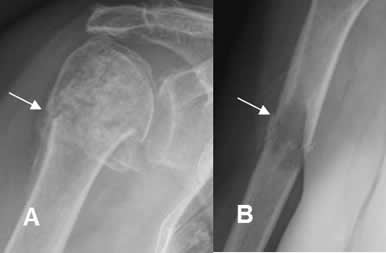

Fig 61. Fractura patológica.

A: Rx AP. Alteración en la densidad de la cabeza del húmero, con matriz condroide, por la presencia de encondroma. Se aprecia fractura transversa y no desplazada a nivel del cuello.

B: Rx AP. Imagen ovalada y radiolúcida en la diáfisis humeral, compatible con quiste simple. Existe fractura asociada, no desplazada y en sentido oblicuo.